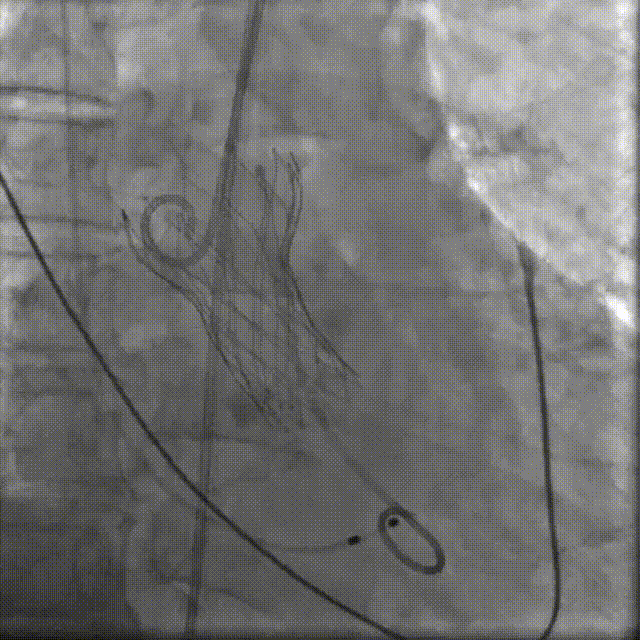

置入猪尾进行根部造影,造影可见根部钙化不均匀,瓣叶活动度低,冠脉灌注良好。

根部造影

22mm球囊预扩,轻微腰征,冠脉显影良好,无造影剂渗漏。

22mm球囊预扩